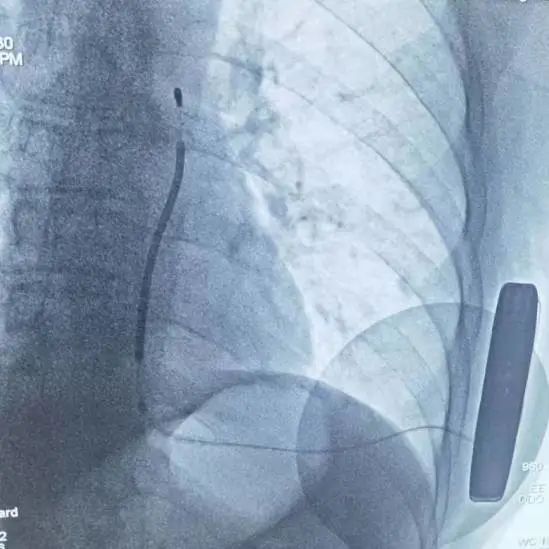

(术后影像)